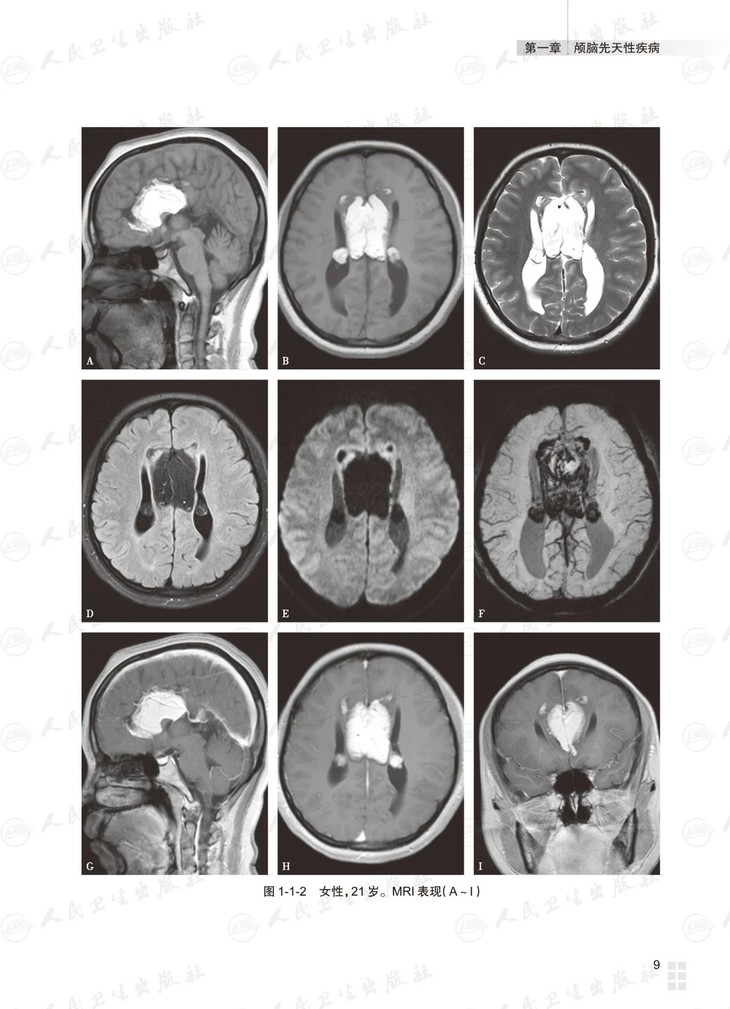

本书总论部分介绍多模态脑功能成像技术及临床应用。各论分为三篇:基础篇为常见颅脑疾病多模态磁共振成像典型病例分析,以复习为主,从疾病的临床与病理入手,解析影像学特征,提供影像诊断思路,最终给出诊断要点;进阶篇为各部位常见颅脑疾病多模态磁共振成像病例讨论,以考查为主,每章讨论颅脑同一部位的多个病例,附有多模态磁共振图像的征象分析、诊断及诊断要点,最后以思维导图的形式展示对该部位疾病的影像诊断思路;高级篇是多模态磁共振成像在颅脑疾病鉴别诊断中的应用,重在对功能成像技术进行横向比较,作出鉴别诊断。